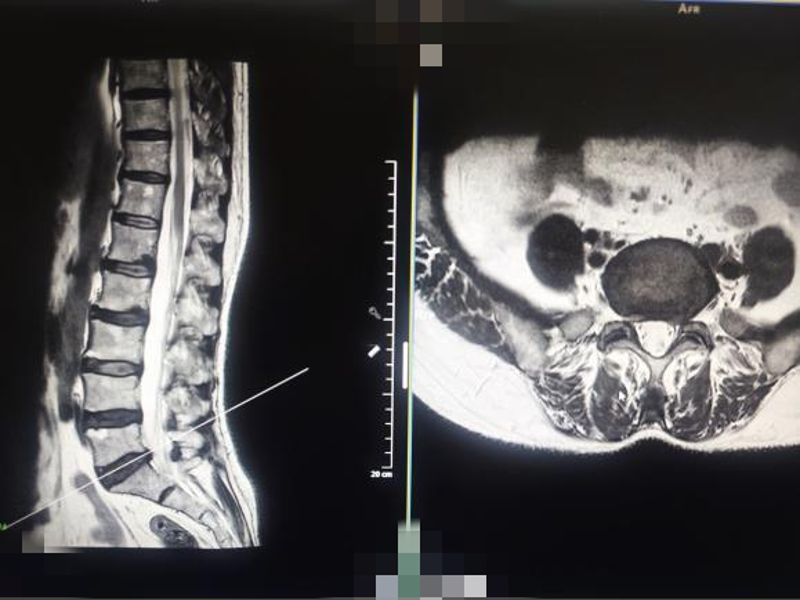

(图为患者术前检查显示的椎间盘突出及退变情况)

蒋凯医生在脊柱与骨科方面有25年临床经验,脊柱疾病治疗经验丰富。经过详细询问病史、查体及完善腰椎MRI检查后,确认患者腰椎间盘突出压迫左侧神经根。嘱患者入院后,完善术前检查,未见手术禁忌,于是决定为何女士采取微创脊柱椎间孔镜手术。